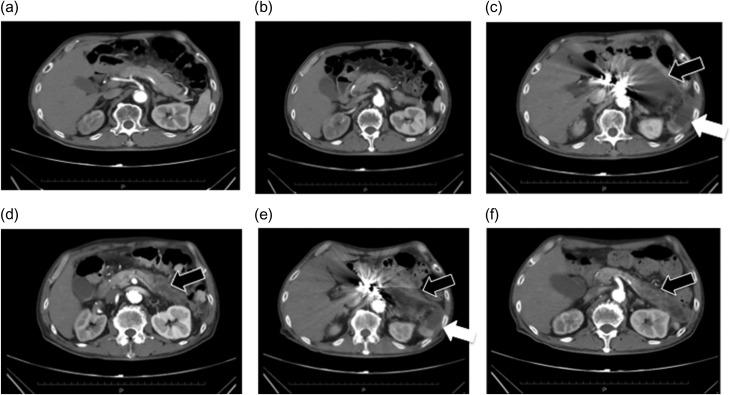

Acute pancreatitis caused by pancreatic ischemia after TEVAR combined with intentional celiac artery coverage and embolization of the branches of the celiac artery.

Covering and embolizing the celiac artery has been reported to be a relatively safe procedure, owing to the rich collateral pathway between the celiac artery and superior mesenteric artery. A 69-year-old man presented with an aneurysm on the distal descending aorta. The proximity of the aneurysm to the celiac artery origin necessitated covering the artery with a stent graft. Additionally, the celiac trunk was short, increasing the risk for Type II endoleak. The origin of the celiac artery was covered after embolization of the branches of the celiac artery. Postoperatively, nausea and abdominal pain appeared, and the amylase level and white blood cell count were elevated. Contrast-enhanced computed tomography and abdominal ultrasonography revealed necrosis and cyst formation in the pancreatic tail, resulting in a diagnosis of acute pancreatitis caused by pancreatic ischemia. Conservative treatment was applied. After discharge, although walled-off necrosis remained, the patient was doing well, without any clinical symptoms.